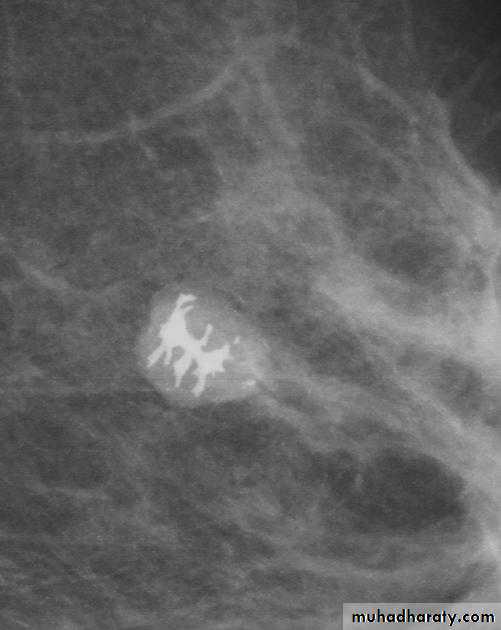

spiculated hyperdense lesion

microcalicifications

Micro calcifications

Micro calcifications are tiny specks of calcium in the breast. Micro calcifications seen on a mammogram are of more concern than macrocalcifications, but they do not always mean that cancer is present. The shape and layout of microcalcifications help the radiologist judge how likely it is that cancer is present.

In most cases, the presence of microcalcifications does not mean a biopsy is needed. But if the microcalcifications have a suspicious look and pattern, a biopsy will be recommended. (During a biopsy, the doctor removes a small piece of the suspicious area to be looked at under a microscope. A biopsy is the only way to tell if cancer is really present.)